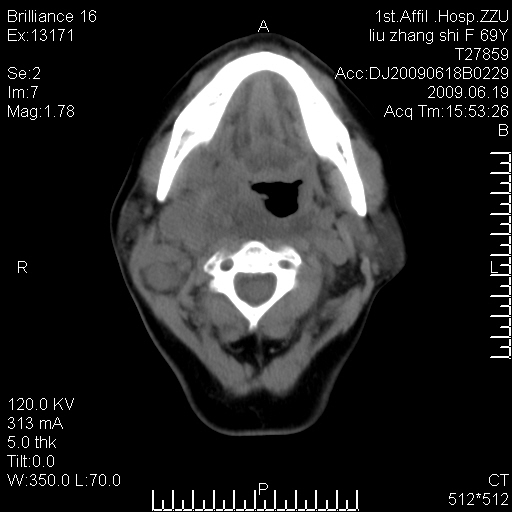

标题: CT26782:女,69岁,颈部占位,3天后公布病理结果。

【病理证实系列】女,69岁,颈部占位,有病理结果,3天后公布。(由于病例时间较久,临床资料不全,请网友见谅)本系列将有几百种常见、少见及罕见病例,均经病理证实。病例资料来自郑州大学第一附属医院。与网友共享,本人有空就发。

甲状腺癌并颈部淋巴结转移。感谢楼主的良苦用心,谢谢。

甲状腺癌并颈部淋巴结转移。

需与鼻咽癌鉴别!

支持甲状腺癌广泛侵及周围结构并颈部淋巴结转移。

鉴别:淋巴瘤、恶性神经源性病变、恶性纤维组织细胞瘤。

病理结果:颈部非霍奇金淋巴瘤。